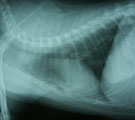

初診時レントゲン。肺野全体に広がるまだらな肺胞浸潤影。 気管支鏡検査より3日後。浸潤影はほぼ消失している。 1年2ヶ月後。この間投薬は一切なかった。肺野は正常。

経過:元気なく軽度の発熱(39.6℃)あり。5日前より突然喘息様症状あり呼吸困難もあるとのことだった。胸部レントゲンでは肺野全体に広がるまだらな肺胞浸潤影がみられた。動脈血酸素分圧は79.2mm Hgとやや低下し軽度の肺機能低下がみられた。感染による肺炎が疑われたが、腫瘍や猫喘息との鑑別の必要もあり気管支鏡検査を行った。粘膜は全体的に浮腫状を呈していた。気管支肺胞洗浄液(RB3, 回収率76.7%)中に細菌・真菌は検出されなかったが好中球の増加(60.25%)がみられた。腫瘍細胞はみられず、喘息を示唆する好酸球もみられなかった。無菌性の気管支肺炎であった。入院にて酸素、気管支拡張剤、去痰剤を投与し、治療初期にのみ抗生剤を投与した。検査より3日後には肺野の浸潤影はほぼ消失し元気食欲がでできた。10日後退院。それから1年2ヶ月後、腫瘍摘出の件で入院した際の胸部レントゲンでは肺野は正常化していた。この間投薬は一切なかった。